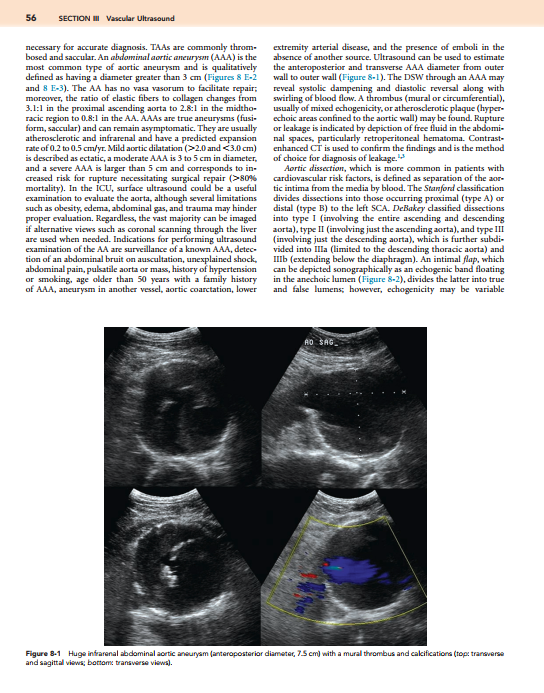

Description